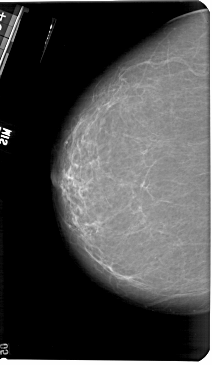

A_1182_1.RIGHT_MLO

RIGHT_MLO LINES 5491 PIXELS_PER_LINE 3421 BITS_PER_PIXEL 12 RESOLUTION 43.5 OVERLAY